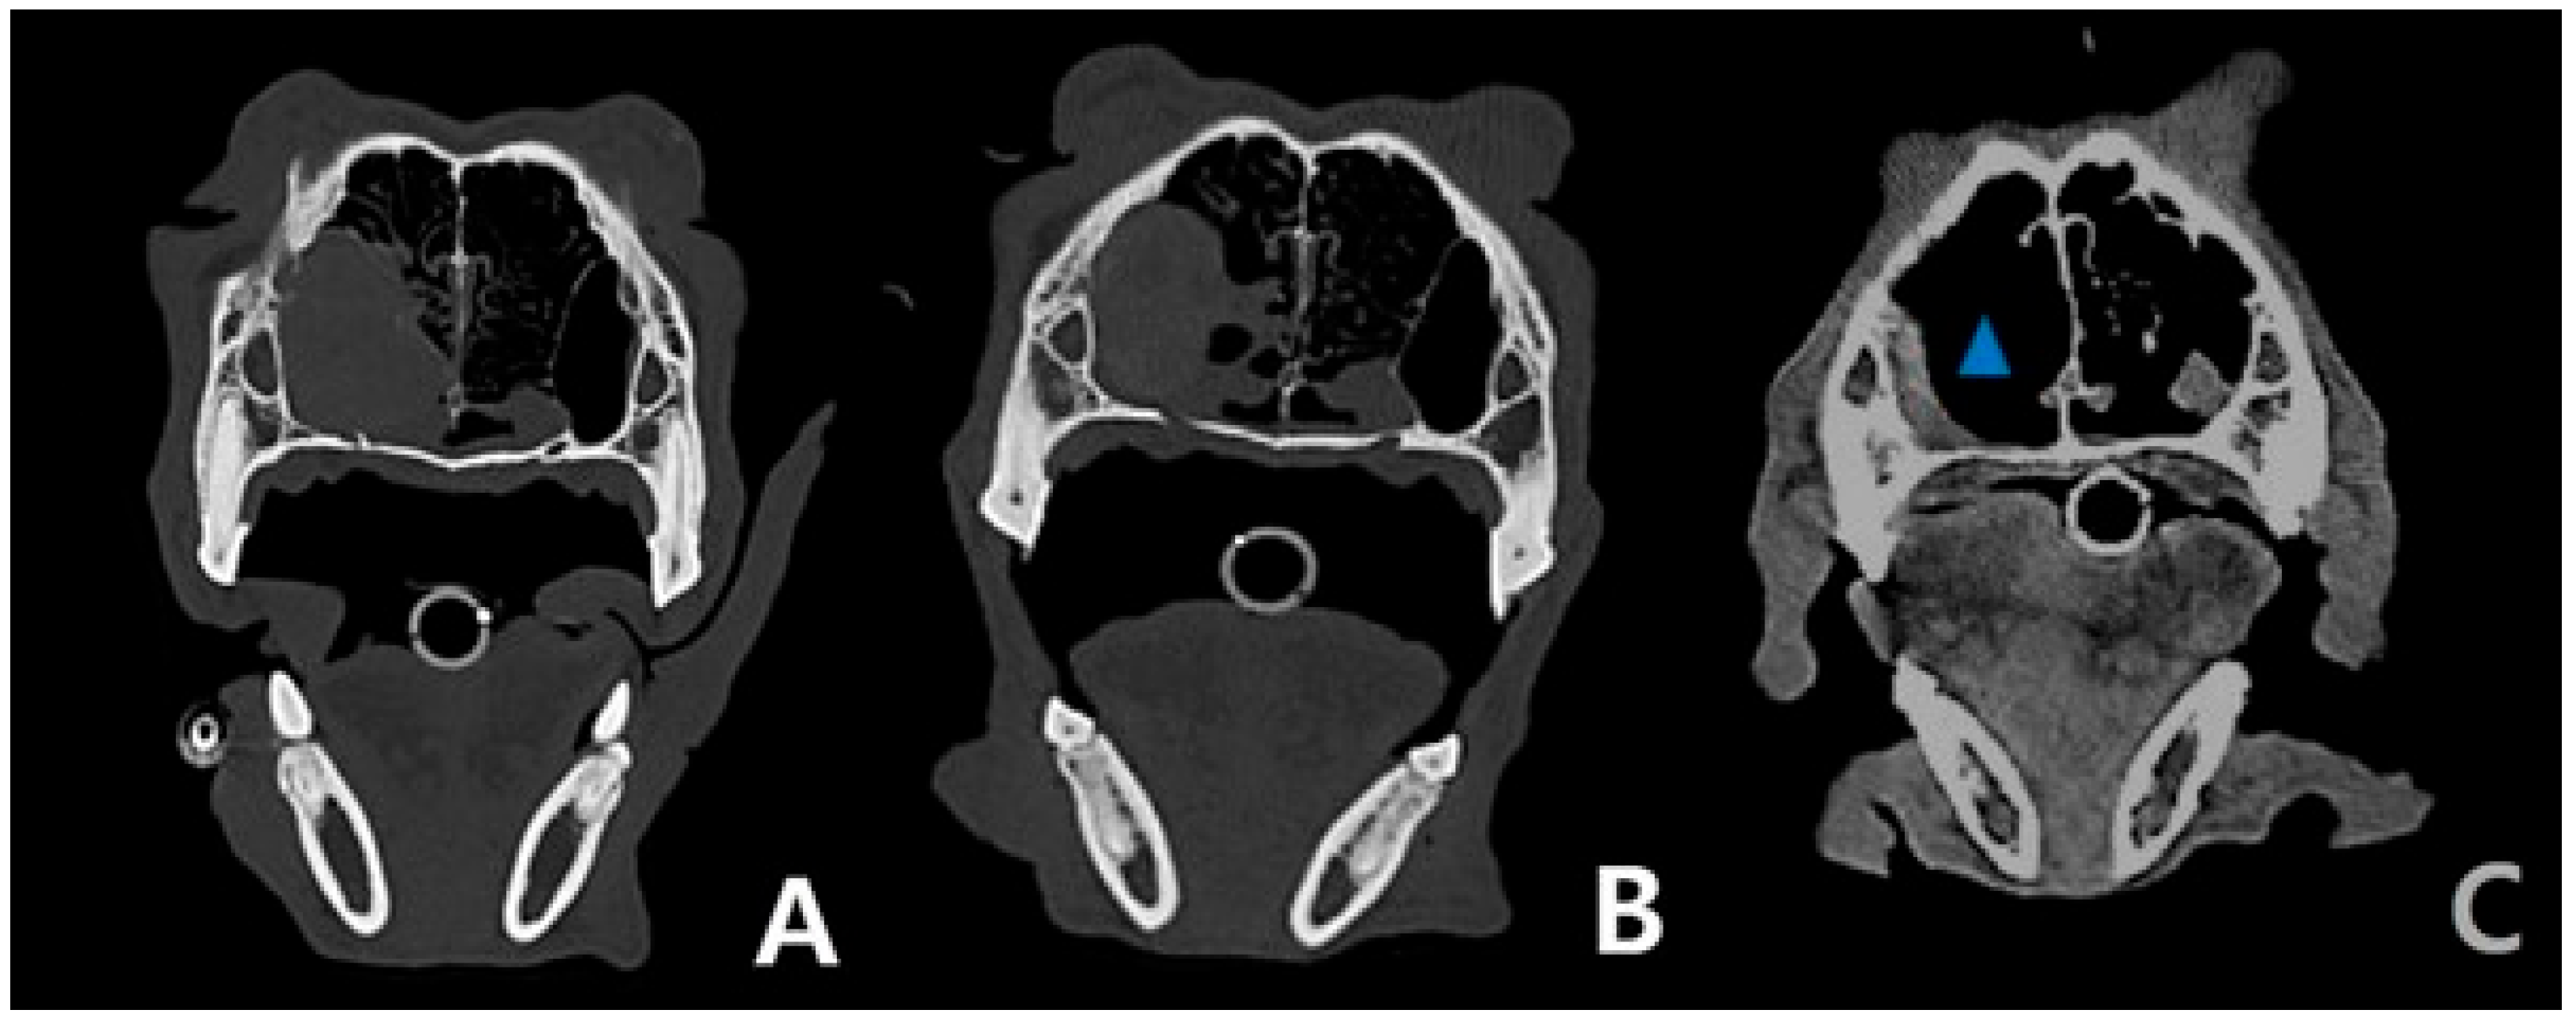

2. Case Description